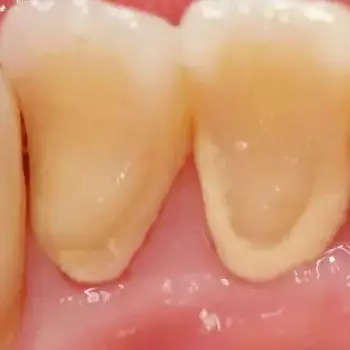

치석 이란, 치구(플라크)와 타액에 포함된 인산이나 칼슘, 음식물 찌꺼기 등이 결합해 치아에 달라붙어 석회화된 것입니다.

치석은 약 80%가 인산칼슘이고 그 외에 단백질이나 탄수화물, 세균의 시체, 음식물 찌꺼기 등이 포함되어 있습니다.